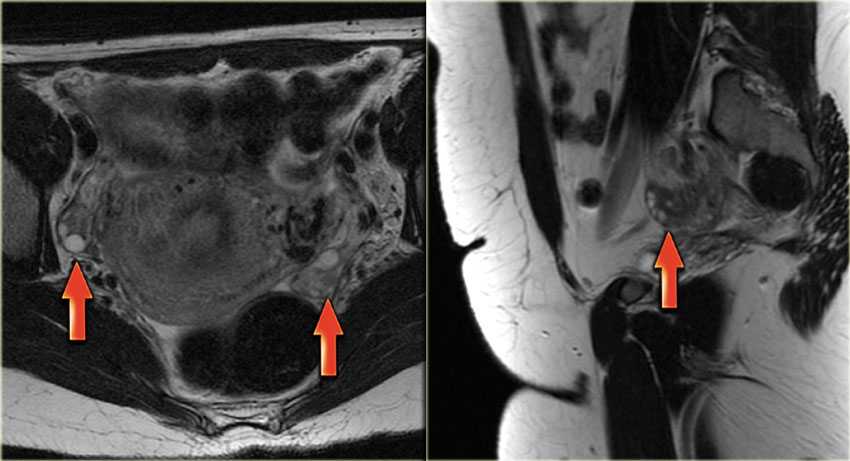

Как выглядят яичники на МРТ? На Т2-взвешенных МР-томограммах Граафовы фолликулы выглядят как гиперинтенсивные (т.е. яркие по сигналу) кисты с тонкими стенками, окруженные стромой яичника, дающей не столь интенсивный сигнал.